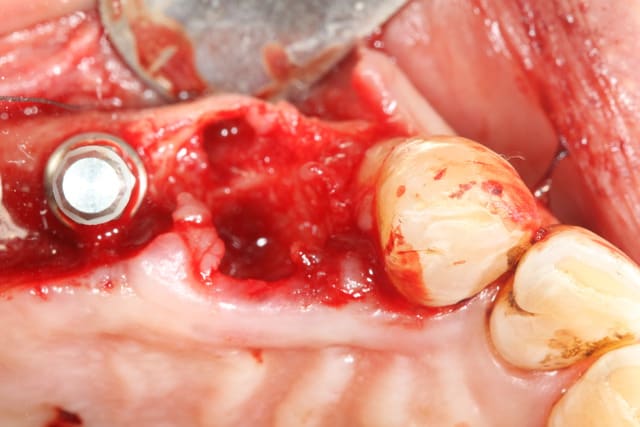

En examinant la paroi vestibulaire de l’alvéole après extraction...j'ai pensé que la résorption faisant l'option implantaire serait plus compliquée par la suite. J'ai donc posé l'implant en 24;

A posteriori je me dit que j'aurai du poser la membrane autour de l'implant pour éviter la compétition cellulaire et optimiser mon comblement.

bravo ! Pour la 24, la prochaine fois commence avec un trépan dans le septum:

tes forets suivant ne seront plus déviés et tu aura un peu d'os à mélanger au Bio-Oss

Ici, pas besoins de membrane car ton défaut osseux est à 4 parois

dommage que tu sois si timide pour la longueur des implants, y'avait de quoi mettre un peu plus long et faire une mise en esthétique immédiate

oui t'as raison, mais comme je ne suis encore rompu au bon positionnement tridimensionnel des implants, j'ai préféré me laisser un peu de marge au cas ou je dévie...